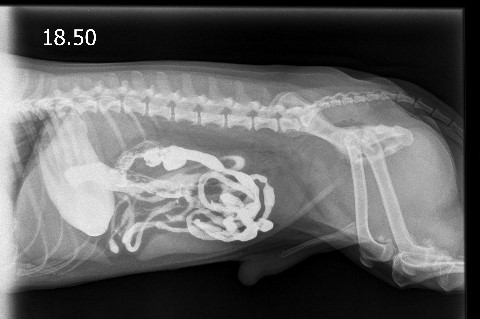

Ein stationärer Aufenthalt kann außerdem für bestimmte Funktionstest z.B. zur Diagnosestellung eines Diabetes insipidus oder eines Cushing, zur Therapiekontrolle eines Diabetes mellitus oder zu Darstellung des Magen-Darm- Traktes mit Kontrastmittel (sog. Kontrastmittelstudie) bei Verdacht auf einen Fremdkörper sinnvoll sein.